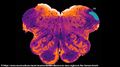

| رسم يوضح مرض پاركنسن رسمه السير وليام ريتشارد گورز من كتابه A Manual of Diseases of the Nervous System المنشور في 1886 | |